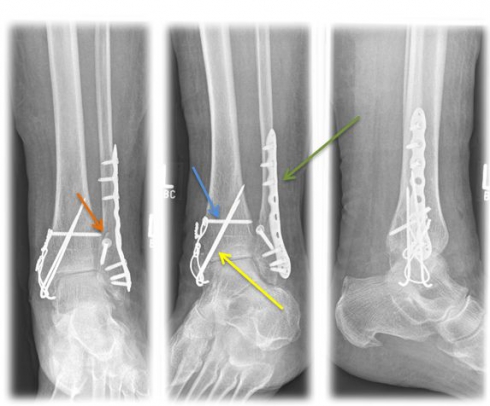

undefined

Fig. 4) Osteosynthetic treatment of a bimallel ankle fracture by means of tension belt osteosynthesis at the inner ankle (yellow arrow), neutralization plate (green arrow) and a traction screw (orange arrow) at the outer ankle as well as an adjusting screw (blue arrow).